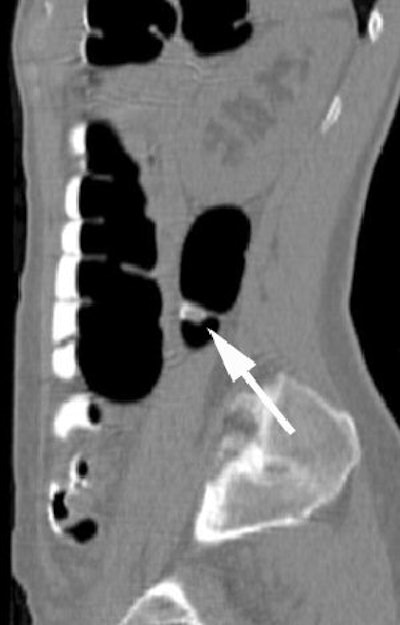

| Endoluminal VC image demonstrates relationship of the polyp (arrow) with colonic haustral fold. Image courtesy of Dr. Riccardo Iannaccone. |

An audience member asked how unprepped colons could end up looking so clean -- at least in the examples shown in the presentation. Iannaccone said the combination of a low-residue diet and mild prep caused by the oral contrast agent produces relatively clean images in some patients.

"Gastrografin has a mild cathartic effect -- a well-known and wanted side effect that produces diarrhea, although it is certainly not ... comparable with standard cathartic preps," he said. "However, in the majority of patients, fecal material was actually present and homogeneously tagged."